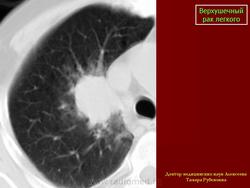

Верхушечный рак легкого

Рентгенологические проявления верхушечного рака легкого обусловлены стадийностью его роста, при которой можно выделить 2 группы.

Первая группа: верхушечный рак без синдрома Панкоста - опухоль не выходит за пределы легочной ткани. Опухолевые узлы округлой или неправильной формы, различных размеров, однородной структуры с бугристой поверхностью и нечеткими контурами, которые в виде тяжей распространяются в прилежащие отделы легочной ткани.Может выявляться неоднородная дорожка к корню легкого в результате перибронхиального роста опухоли в сторону корня, при этом отмечается неравномерное сужение просвета сегментарного бронха.

Следует отметить, что при железистых раках (АДКЛ) опухоль длительное время не выходит за пределы легочной ткани и не вызывает клинико-неврологических синдромов, однако, выявляются регионарные и отдаленные метастазы. Метастатическое поражение может проявляться увеличением ипсилатеральных лимфатических узлов корня легкого и средостения, над - и подключичных областей, иногда диссеминированным поражением легочной ткани.

Вторая группа: верхушечный рак с синдромом Панкоста. Клиническая картина характеризуется присоединением неврологической симптоматики различной степени выраженности. При рентгенологическом исследовании выявляется распространение опухолевого процесса за пределы легочной ткани, с вовлечением прилежащих структур средостения, мягких тканей грудной стенки, ребер и позвонков. Размеры опухолевых узлов от 3,0 см и более, имеющих округлую, овальную или неправильную форму, структура их однородная или неоднородная. Наружные контуры нечеткие, за счет распространения опухолевой инфильтрации на прилежащие органы и ткани: плевру, мягкие ткани грудной стенки, ребра, средостение, позвонки. Внутренняя поверхность опухоли может быть крупнобугристая с четкими, неровными или нечеткими контурами.

Неоднородность структуры опухоли обусловлена обычно неравномерной плотностью узла, иногда деструкцией опухолевой ткани с формированием полости распада.

Истинная степень распространенности опухолевого процесса на прилежащие ткани средостения, ребра и позвонки устанавливается при проведении МРТ исследования.

Следует отметить, что имеются различия в клинико-рентгенологических проявлениях верхушечного рака в зависимости от гистологического строения опухоли.Так при ПКРЛ преобладает местное распространение опухолевого процесса, а при АДКЛ выявляются отдаленные метастазы, появление которых не зависит от размеров первичной опухоли.